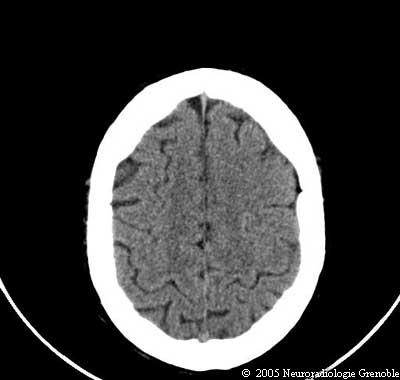

Radioanatomie TDM de l'encéphale

TDM cérébrale sans injection